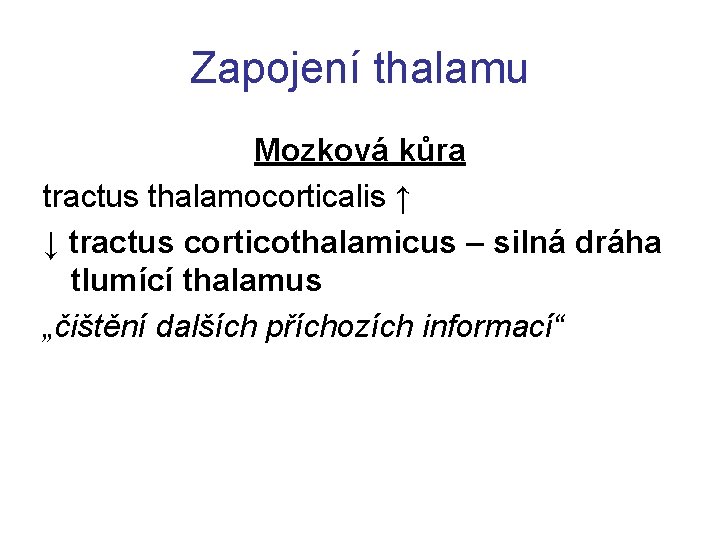

Zapojení thalamu Mozková kůra tractus thalamocorticalis ↑ ↓ tractus corticothalamicus – silná dráha tlumící thalamus „čištění dalších příchozích informací“